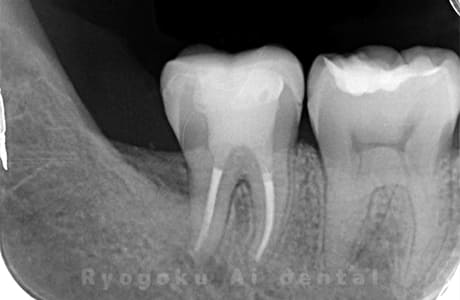

Case03

-

- 原因

- 急性化膿性根尖性歯周炎

- 治療期間

- 2ヶ月

- 治療内容

- マイクロエンド

- 治療費用

- 121,000円

黙っていても痛みが出るとのことで来院した患者様です。本治療は症状もあるため、抜髄治療をマイクロエンドで行いました。

<リスク・副作用>

術後は痛み、腫れ、痺れなどの副作用が生じる場合があります。症状が再発する可能性があります。